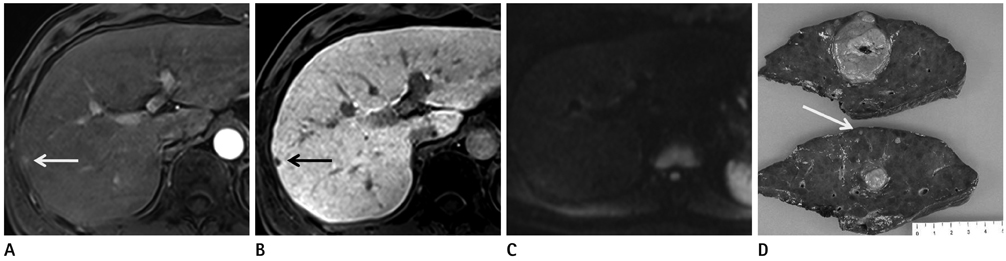

To compare diffusion-weighted imaging (DWI) and gadoxetic acid-enhanced (Gdx) magnetic resonance imaging (MRI), whether alone or in combination, for the detection of hepatocellular carcinoma (HCC) by using 3 T.

84 HCCs in 66 patients (57 men, 9 women; mean age 69.2 years) were examined using 3 T MRI. DWI (b values 0, 50, and 800 sec/mm2) and dynamic gadoxetic acid-enhanced MRI as well as hepatobiliary phase were performed. Images were retrospectively reviewed by two radiologists to compare the diagnostic performances of DWI and Gdx MRI alone and in combination for the detection of HCC. Alternative free response receiver operating characteristic analysis and comparison of sensitivities were used for statistical analysis.

The sensitivity of Gdx set (73/84, 87%) was significantly higher than that of DWI set (60.5/84, 72%) for both observers. The Az values of DWI and Gdx MRI for the detection of HCC were not statistically significant for either observer (Az for DWI = 0.818 and 0.864, Az for Gdx MR = 0.902 and 0.842, respectively, p = 0.107 for observer 1 and p = 0.738 for observer 2). The combination of both techniques did not increase the sensitivities of detecting HCC in either observer. When lesions smaller than 2 cm were considered, the DWI set yielded a significantly lower sensitivity as compared with either the Gdx set alone or the combination set.

Gadoxetic acid-enhanced MRI was better than DWI for detection the HCC by using 3 T MRI. The combination of DWI and Gdx MRI did not contribute to the successful detection of HCC.

Figure